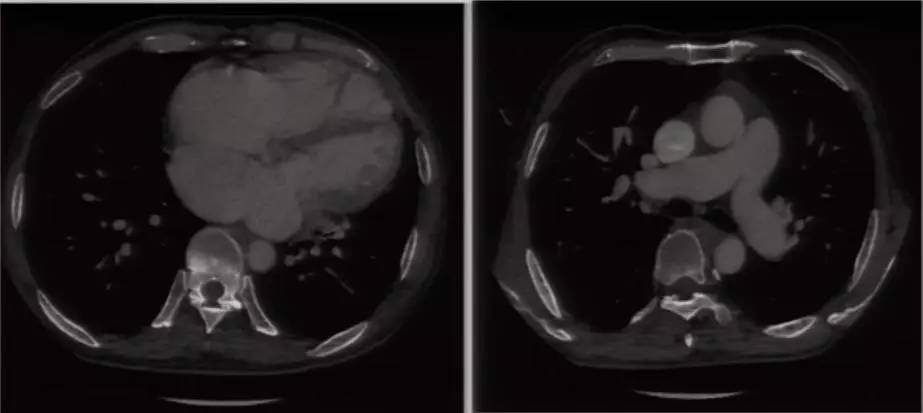

进一步完善相关检查:胸片提示双肺淤血,肺血增多,升主动脉及主动脉结增宽,肺动脉段平直,全心增大,心胸比0.63(图6)。复查超声心动图可见LA 58 mm,LV 53 mm,LVEF 60%,RV 41 mm;房间隔卵圆孔回声分离3 mm,后下部薄弱,探及数处回声脱落,大者约18 mm;二尖瓣前叶发育异常,收缩期瓣体向左房弯曲,致对合不拢。超声提示先天性心脏病(先心病)、Ⅱ孔型房间隔缺损(多发)、卵圆孔未闭、房水平左向右分流 ,二尖瓣脱垂并中大量反流,三尖瓣少中量反流,肺动脉高压49 mmHg。心脏CT提示先心病、房间隔缺损(下腔型),二尖瓣脱垂,双房右室扩大,少量心包积液(图7)。

图7

进一步完善心脏MRI和右心导管检查。心脏MRI提示全心增大,LVEF 42%,RVEF 17%,右室整体收缩运动明显减弱,心包无增厚,二尖瓣脱垂,二尖瓣关闭不全(中重度),先心病、房间隔缺损,肺循环高压。右心导管检查可见肺动脉压56/20/31 mmHg、左房压22/27/20 mmHg、分流比例(Qp/Qs)3.16、肺血管阻力0.96 Wood U;提示单纯毛细血管后肺动脉高压,左心疾病导致肺动脉高压[依据:肺动脉压56/20/31 mmHg,肺动脉楔压(左房压代替)20 mmHg,肺动脉舒张压-肺动脉楔压=0 mmHg,肺血管阻力≤3 Wood U]。本例患者虽然有先心病、房间隔缺损,证实房水平左向右分流,但未导致第Ⅰ类肺动脉高压,因此肺动脉高压非先心病、房间隔缺损所致。

思考三:至此,诊断思路又发生改变。上述已证实肺动脉高压非先心病所致,那么其是否为左心疾病相关肺动脉高压?如此考虑的话,患者轻度升高的肺动脉压(56/20/31 mmHg)又和其右心扩大,右心衰不平行。此外,超声心动图提示的左房大(58 mm)、右心导管检查提示的左心疾病致肺动脉高压等检查结果均提示存在左心疾病(左心心肌病?瓣膜病?)。综上,本例患者初步考虑双心同时受累。